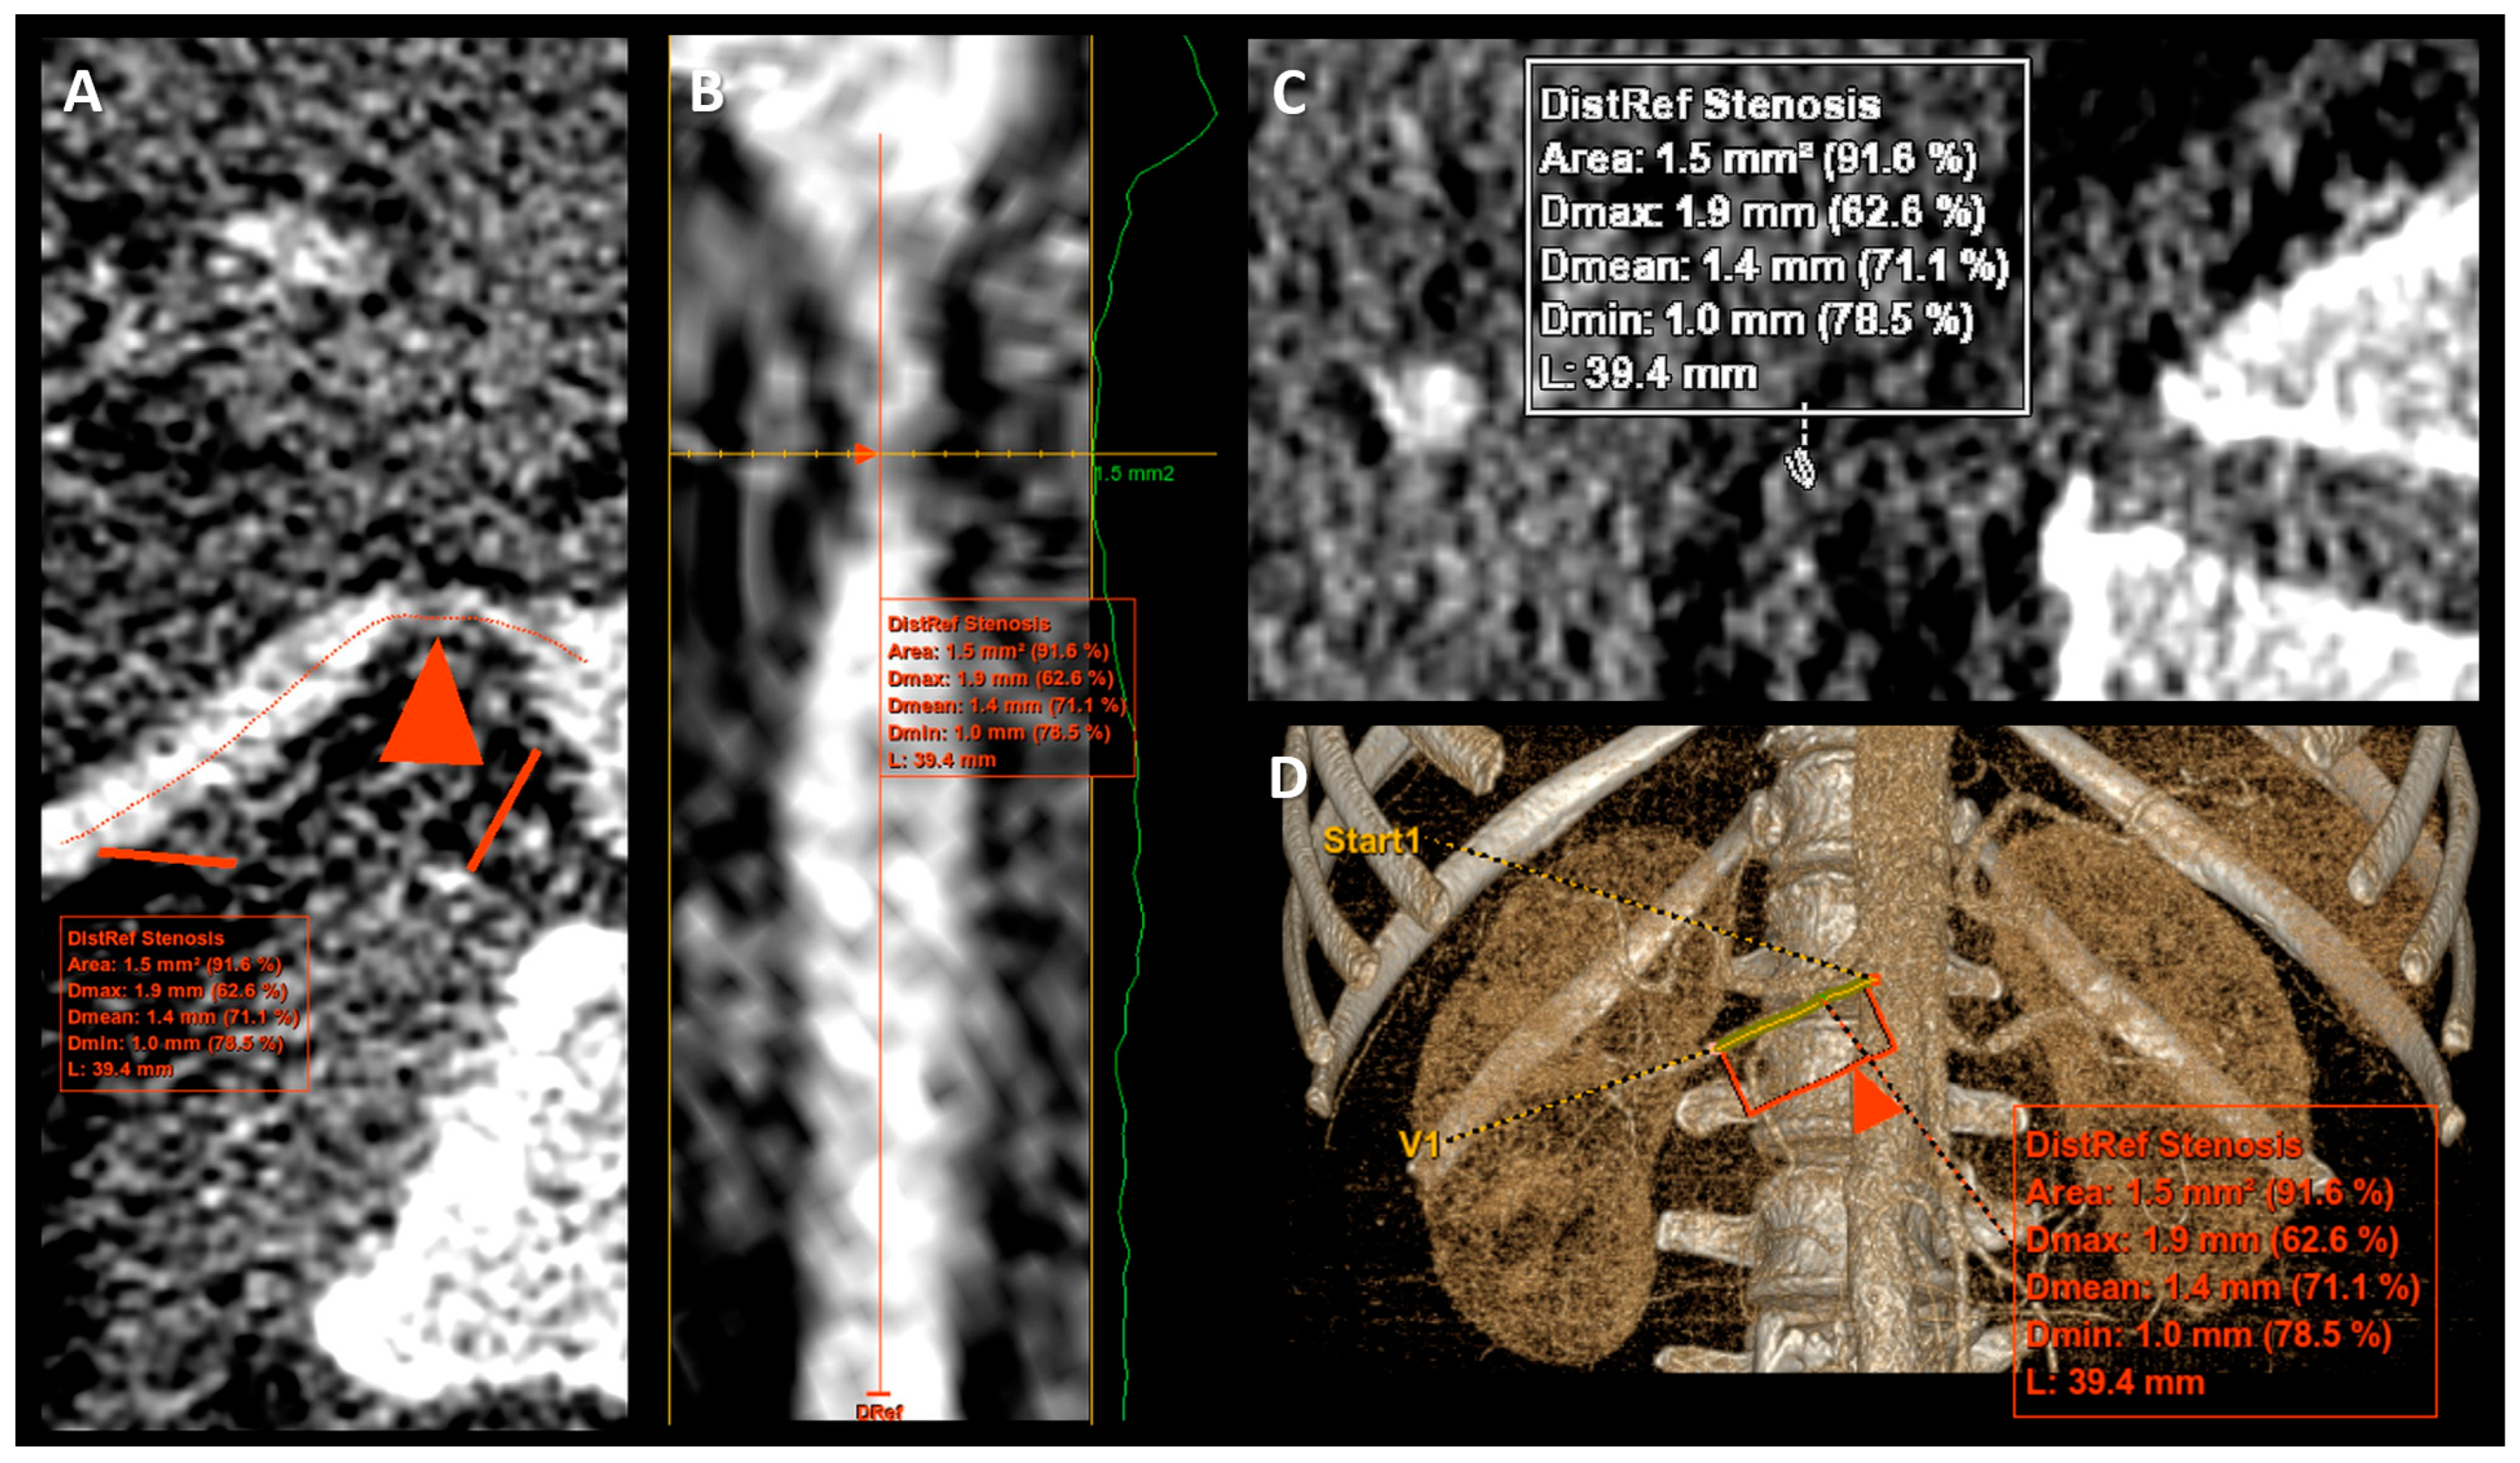

2.2.2. Renal Artery Stenosis Measurement